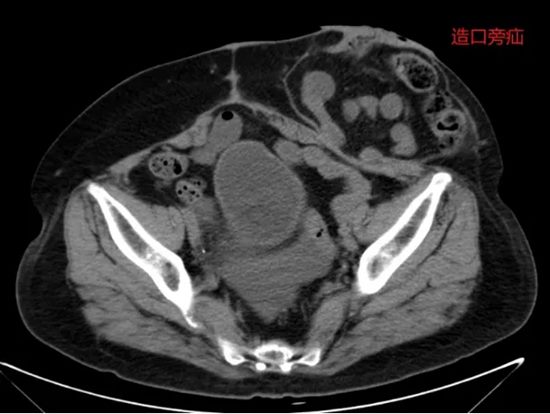

病例四:宫颈癌术后肠瘘+造口旁疝,一次微创手术解决两大难题

病情简述:59岁女性,宫颈癌术后第3天并发乙状结肠瘘。

诊疗破局:团队急诊行腹腔镜手术控制感染并造口。半年后患者要求还纳造口,术前发现合并造口旁疝。经周密规划,在一次腹腔镜手术中同时完成“造口还纳”与“疝修补术”,避免了两次手术创伤。

技术体现:从急诊处理到远期重建,微创外科贯穿始终,体现了系统性治疗的前瞻性。